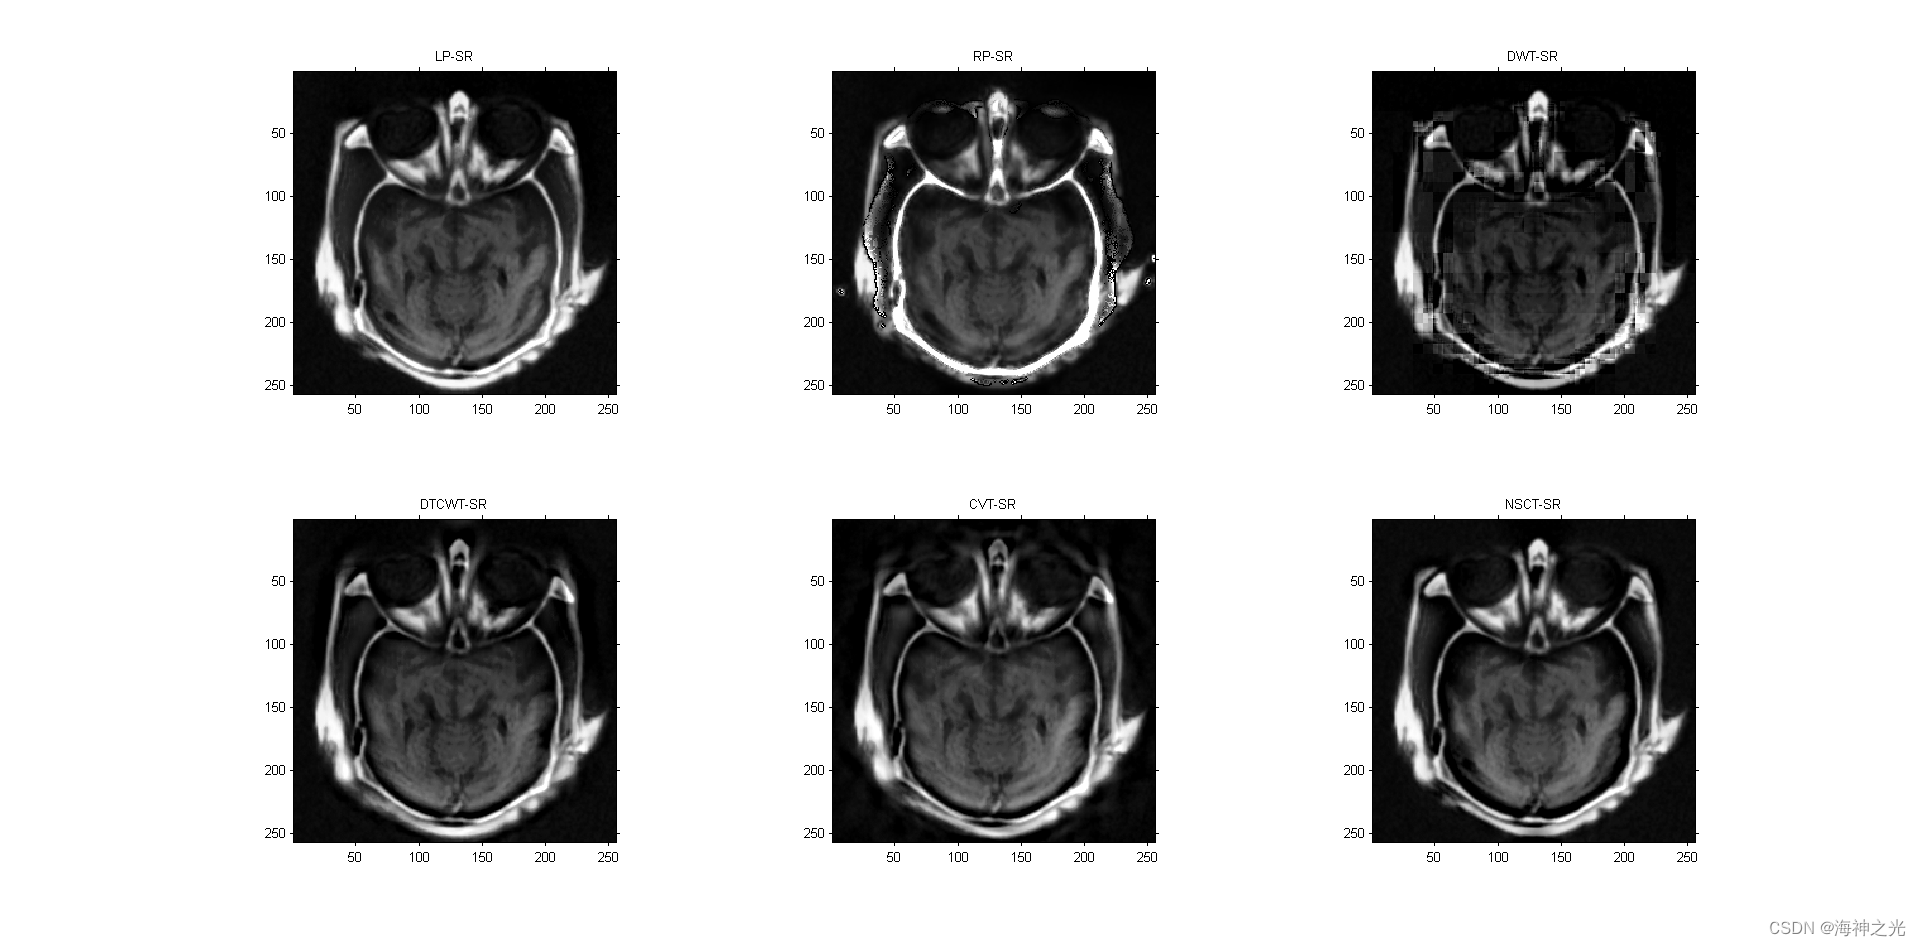

⛄三、运行结果